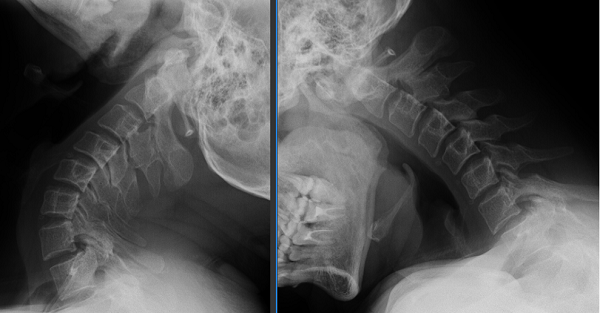

46岁的贾先生曾为此走了不少弯路,反复吃药、针灸都只能暂时缓解。最近一个月,症状加重,他经朋友介绍来到玉溪市人民医院骨外一科就诊。根据贾先生的病情描述,骨外一科接诊医师对其进行了详细的体格检查,并开具了相关检查,确诊为寰枢关节脱位(A型颅底凹陷),还合并寰椎发育畸形。

图片1